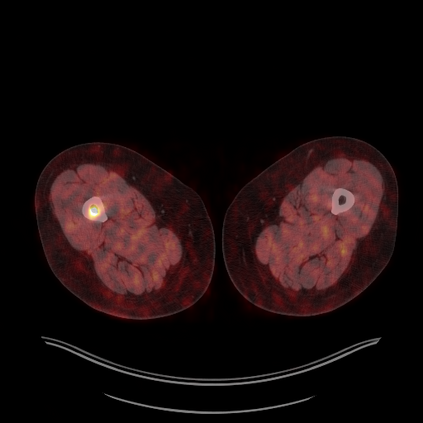

Medical images play a crucial role in assisting diagnosis, remote consultation, and academic research. However, during the transmission and sharing process, they face serious risks of copyright ownership and content tampering. Therefore, protecting medical images is of great importance. As an effective means of image copyright protection, zero-watermarking technology focuses on constructing watermarks without modifying the original carrier by extracting its stable features, which provides an ideal approach for protecting medical images. This paper aims to propose a fragile zero-watermarking model based on dual quaternion matrix decomposition, which utilizes the operational relationship between the standard part and the dual part of dual quaternions to correlate the original carrier image with the watermark image, and generates zero-watermarking information based on the characteristics of dual quaternion matrix decomposition, ultimately achieving copyright protection and content tampering detection for medical images.